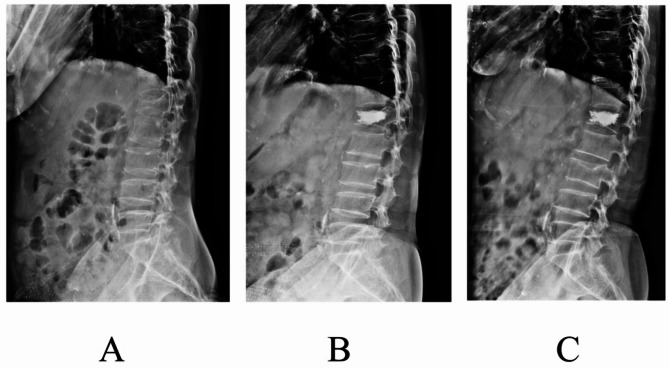

Results: There were no significant differences in baseline characteristics between the two groups, indicating comparability (P > 0.05). All surgeries were completed successfully without complications such as nerve injury or pedicle fracture. No significant differences were found between the groups in terms of operative time, intraoperative bleeding, or radiation frequency (P > 0.05). However, the amount of bone cement injected was significantly greater in the TPPA group compared to the CTPA group (P < 0.05). At 1 day postoperatively, the VAS score and ODI in the TPPA group were significantly lower than those in the CTPA group (P < 0.05), indicating better immediate pain relief and function. No significant differences in VAS or ODI were observed between the groups at preoperative, 3-month, 6-month, or 12-month time points (P > 0.05). Both VAS and ODI scores showed steady improvement within each group, with significant differences between all consecutive time points (P < 0.05). The Beck Index at both 1 day and 12 months postoperatively was significantly higher in the TPPA group compared to the CTPA group (P < 0.05). Within-group comparisons also showed significant improvement in the Beck Index at both postoperative time points compared with preoperative values (P < 0.05). Additionally, the TPPA group demonstrated a significantly higher rate of satisfactory bone cement distribution than the CTPA group (P < 0.05).

Conclusions: In the treatment of OVCF with PKP, the TPPA demonstrated comparable surgical safety to the CTPA. However, TPPA offered advantages in achieving better bone cement distribution, more effective immediate postoperative pain relief, and superior restoration and maintenance of the height of the injured vertebral body.